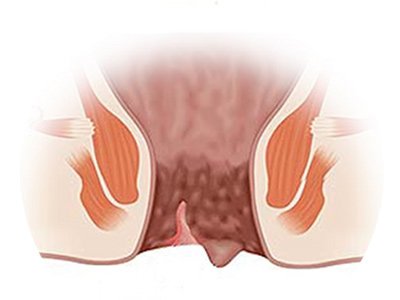

Hemorroidas

Fissura anal

Fístula anal e abscessos

Hemorroidectomia tradicional

Ligadura elástica de hemorroidas

Esfincterotomia anal para fissura anal